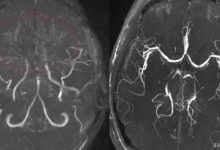

Beyin omurilik sıvısını (BOS) toplamak için bir spinal musluk (lomber ponksiyon) da yapılabilir. Beyin omurilik sıvısındaki dopamin ve serotonin seviyeleri, AADC eksikliğini teşhis etmeye yardımcı olabilir.